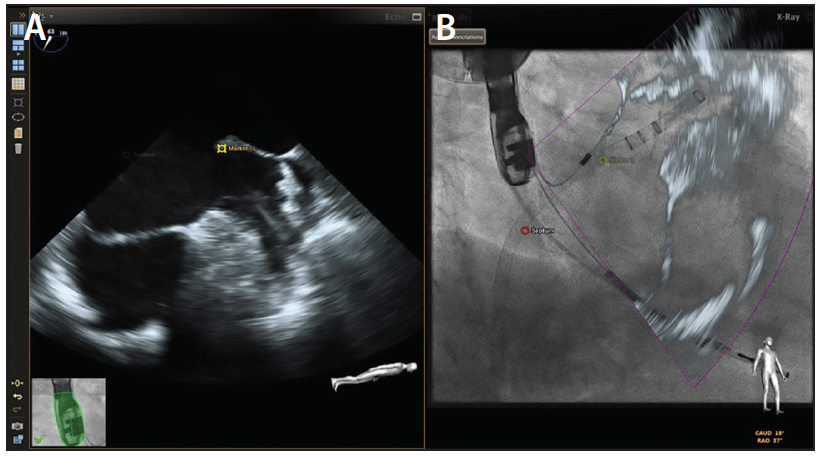

Echocardiographic-Fluoroscopic Fusion Imaging

Due to the complex 3D nature of the LAA, the implanter is essentially required to perform real-time 3D mental integration of fluoroscopic and echocardiographic data while incorporating tactile feedback to successfully execute LAAO. This has led to the development and use of echocardiographic-fluoroscopic fusion imaging technology.40 The EchoNavigator platform (Philips) allows real-time TEE-fluoroscopic coregistration, thereby empowering the interventionalist to execute precise catheter and device manipulations while visualizing cardiac soft tissue anatomy—identifying important landmarks (depicted by fiducial markers) and assessing color flow Doppler information. Using fusion imaging, the target TSP location can be tagged by placing a fiducial marker, which allows the interventionalist to precisely perform the puncture and access the left atrium (Figure 6). Fiducial markers can also be placed at the ostia of the LAA and left superior pulmonary vein. The selected TSP location, when coupled with an appropriately shaped Watchman guiding catheter, allows successful cannulation of the LAA. With the guiding catheter in the left atrium, real-time 2D echocardiographic superimposition over fluoroscopy allows the interventionalist to visualize the normally invisible cardiac soft tissue structures, enabling precise hand-eye coordination and engagement of the LAA. Coregistration also permits advancement of a pigtail catheter into the appropriate lobe of the LAA to the desired depth, which in turn allows advancement of the guiding catheter over the pigtail catheter into the LAA (Figure 7). These steps are crucial when deploying the appropriately sized device at a depth that ensures stable anchoring and a complete seal. Additional technologies such as CT-fluoroscopic fusion are also being actively developed and investigated.

Figure 6. A fiducial marker (“Marker 1”) is placed over an appropriate location on x-plane transesophageal images (A), and the same translates to a corresponding location on anteroposterior fluoroscopic imaging (B) to guide TSP.